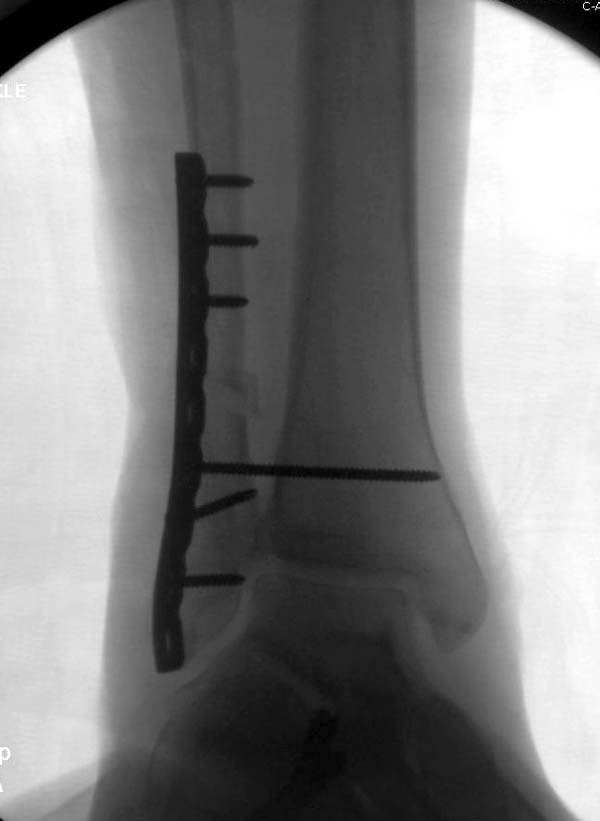

Здесь представлено решение похожей проблемы. Больной в течение года

лечился консервативными мерами, и боли в голеностопе были основным

показанием к операции.

Проведена обычная стандартная процедура по исправлению

неудовлетворительного состояния голеностопного сустава, где кроме

удлинения малоберцовой с применением compression tension device за

проксимальный конец пластины, проведено замещение трикортикальным

графтом из крыла, освобождение синдесмоза и медиальной щели от

фибротических масс с фиксацией.